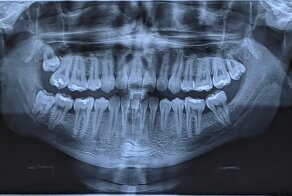

Чушь полная. Титан для имплантации точно так же рентгеноконтрастен как и любой металл. На снимке - 4зубных имплантата сразу после установки.